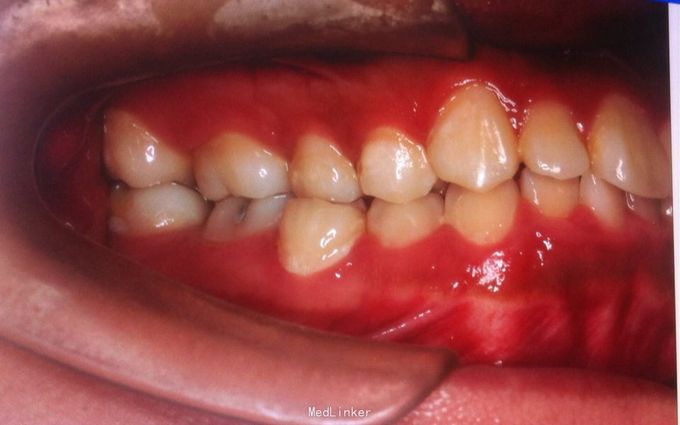

恒牙期 左侧磨牙中性关系,右侧远中关系 前牙三度深覆合 上合牙列中度拥挤,下颌重度拥挤 下颌中线偏右 关节有弹响

安氏二类,牙列拥挤 拔牙矫治,拔除14、24、34、44,强支抗,排齐整平上下牙列,矫治后磨牙中性关系,前牙覆合覆盖正常,面型略改善